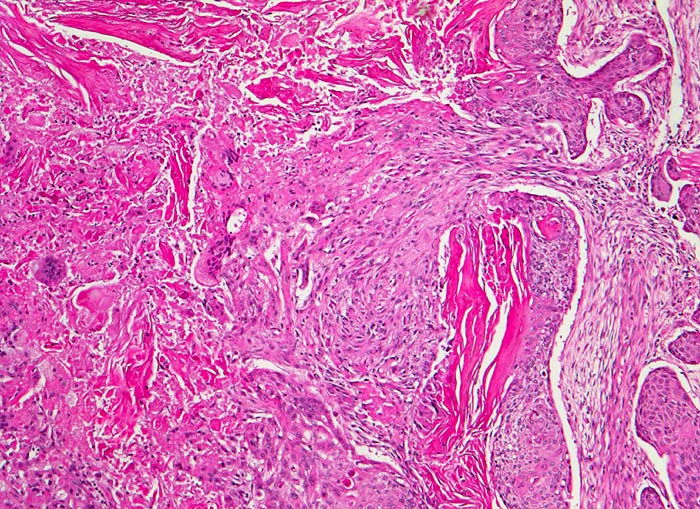

verhornendes Plattenepithelkarzinom

Das Tumorgewebe bildet solide Zellstränge, welche eingebettet sind in ein lockeres desmoplastisches Stroma. Im Zentrum der Zellstränge grosse Mengen von Hornlamellen, welche teilweise nekrotisch zerfallen.

Zentrales Bronchuskarzinom des rechten Lungenoberlappens von 5cm Durchmesser. Lungenoberlappenresektion.

100